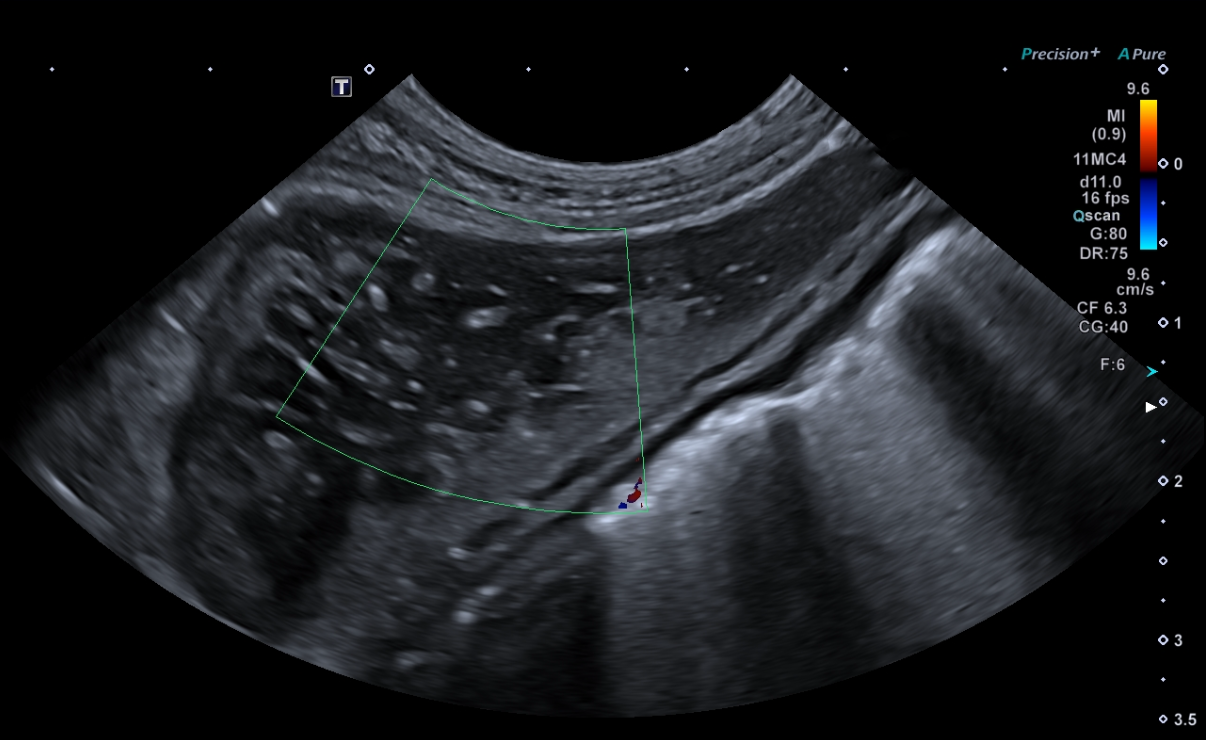

Exposé théorique (par vidéoprojection) de sémiologie échographique explicitant les signes à rechercher et l'interprétation des principales lésions hépatiques et spléniques.

Apprentissage d'un raisonnement échographique à partir de vidéos de cas cliniques pathologiques du foie et de la rate : Identification de la lésion, description avec les termes appropriés, synthèse des anomalies observées et diagnostic différentiel.